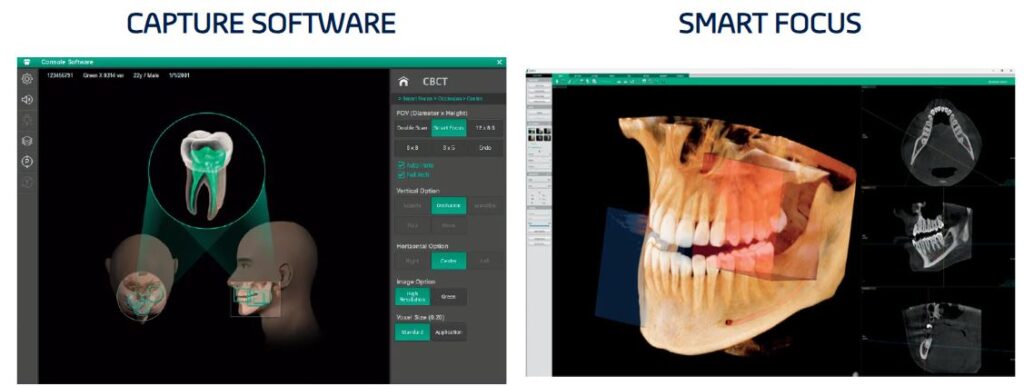

Smart Focus : 1 Scan, 5 Images

With Green X 12, you will get high-resolution images of multiple treatment areas with a single shot. With 1 scan, you get 5 different high-resolution images: three 4×4, one 12×8.5 image and one Auto PANO image. Other advantages are minimal X-ray exposure to the patients and less work for staff, which means a faster and more efficient workflow.

- Smart Focus: 1 scan, 5 images (one 12×8.5, three 4×4 and one Auto Panoramic image)

- Highest Resolution Endo solution with 0.05mm Voxel Size (4×4 Endo mode)